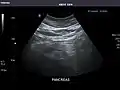

Left kidney

Kidneys: Right and left kidneys measure 11.5 cm and 12 cm in length respectively. No hydronephrosis. Small left lower pole kidney cyst.